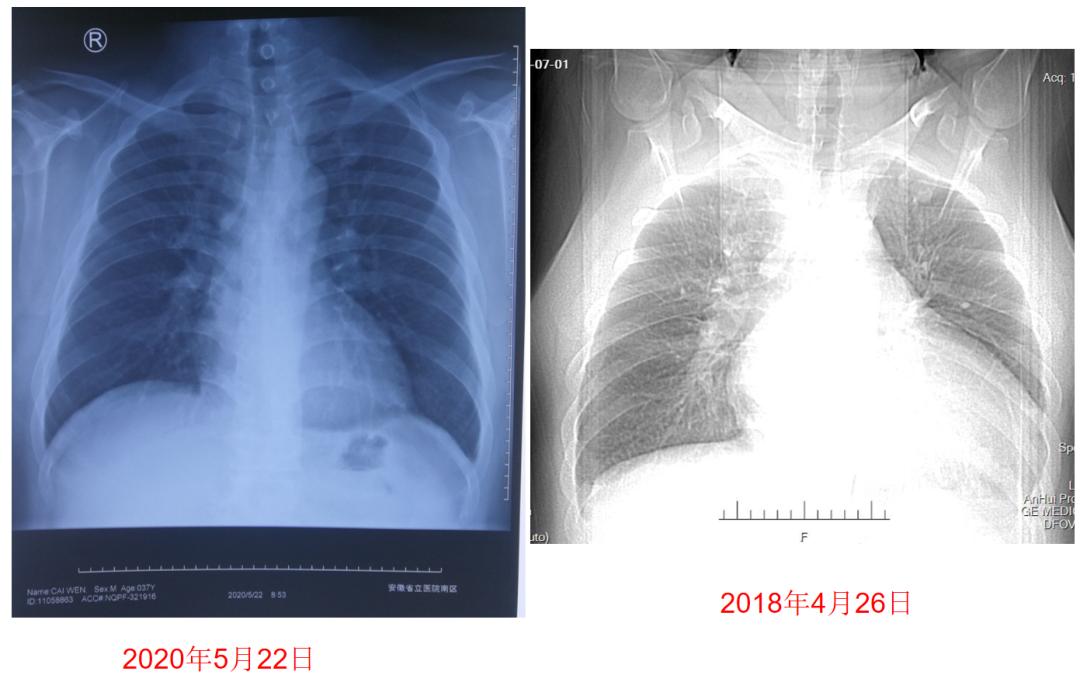

图5:患者药物治疗前后胸片检查对比

③出院后2年随访。患者日常无活动后胸闷、气促,无夜间阵发性呼吸困难、能做家务、接送女儿上学,未再住院,通过适度运动结合节食,体重再次减轻25公斤,目前体重110公斤。出院后2年复查LVEF示53%,由于患者近12个月心脏彩超无明显变化,将沙库巴曲缬沙坦加量至200 mg bid,期待进一步改善。

②出院后1年随访过程。出院后2月随访时,患者血压保持于100~130/60~80 mmHg,将沙库巴曲缬沙坦加量至100 mg bid,复查LVEF上升至37%。

用药1年后,左房内径(LA)、左室内径(LV)、右室内径(RV)、右房内径(RA)、肺动脉收缩压(SPAP)等心脏重构指标均明显改善,LVEF上升至52%(表2)。